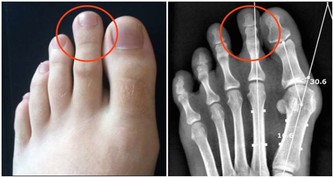

1名40多歲男性幾年來接受健檢時,都被檢驗出有貧血現象,但因工作忙碌並未理會,沒想到近來出現頭暈、容易疲勞,甚至吃不下飯等現象,就醫檢查竟已是胃癌末期合併肝臟轉移;台大醫院新竹分院血液科醫師林明恩指出,貧血千萬別忽視,恐是身體警訊徵兆。